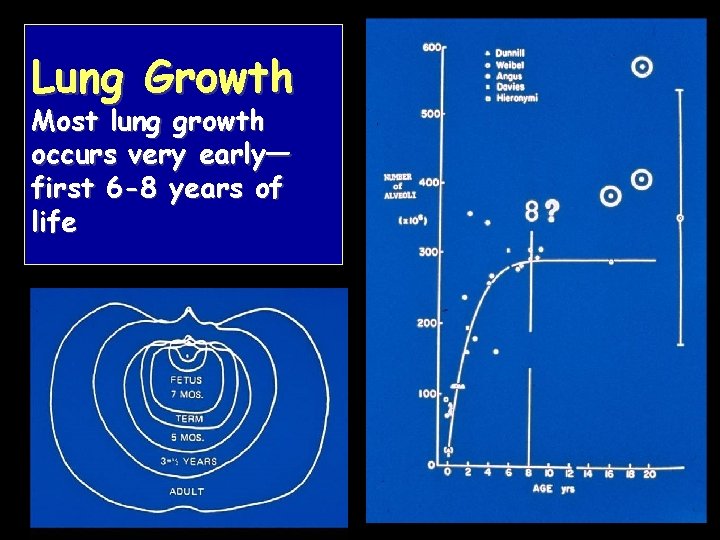

Lung Growth Most lung growth occurs very early— first 6 -8 years of life